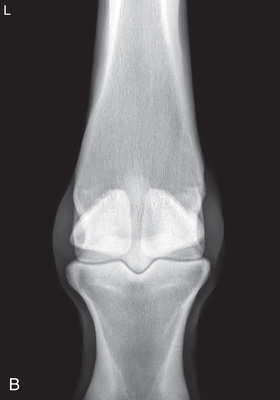

| Stifle | Lateromedial (LM) | Lateral (L) |

| Caudoproximal-craniodistal (CdPr-CrDi) | Caudocranial (CdCr) | |

| Stifle | Caudocranial CdCr (Standard) | Caudoproximal-craniodistal standing (CdPr-CrDi) | Weight-bearing with limbs evenly on ground and vertical cassette against cranial aspect of patella at right angle to body wall, placed as far proximal and pushed as far medially as abdomen permits. | Caudal to the joint and directed downward to obtain a “tunnel” view of the distal femur. |

| Lateral (Standard) | Lateromedial | Weight-bearing with limbs evenly on ground and cassette against medial aspect of joint. | Laterally, parallel to the ground and centered distal and caudal to the patella. | |